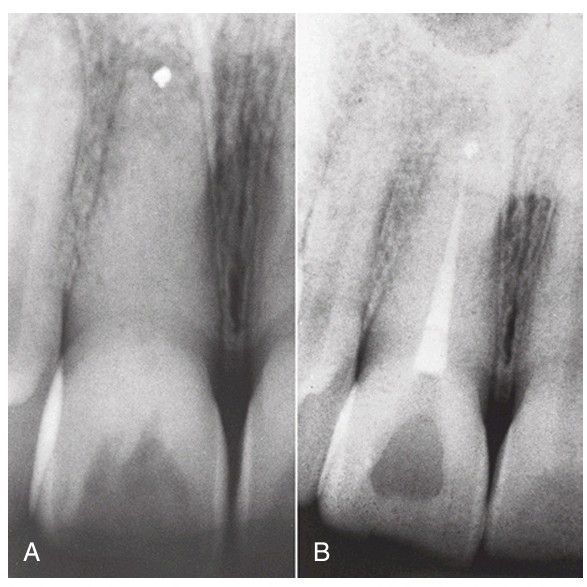

A) Inadequate root end resection and root end filling have failed to seal the apex. (B) Root canal treatment is readily accomplished, with good chance of success.